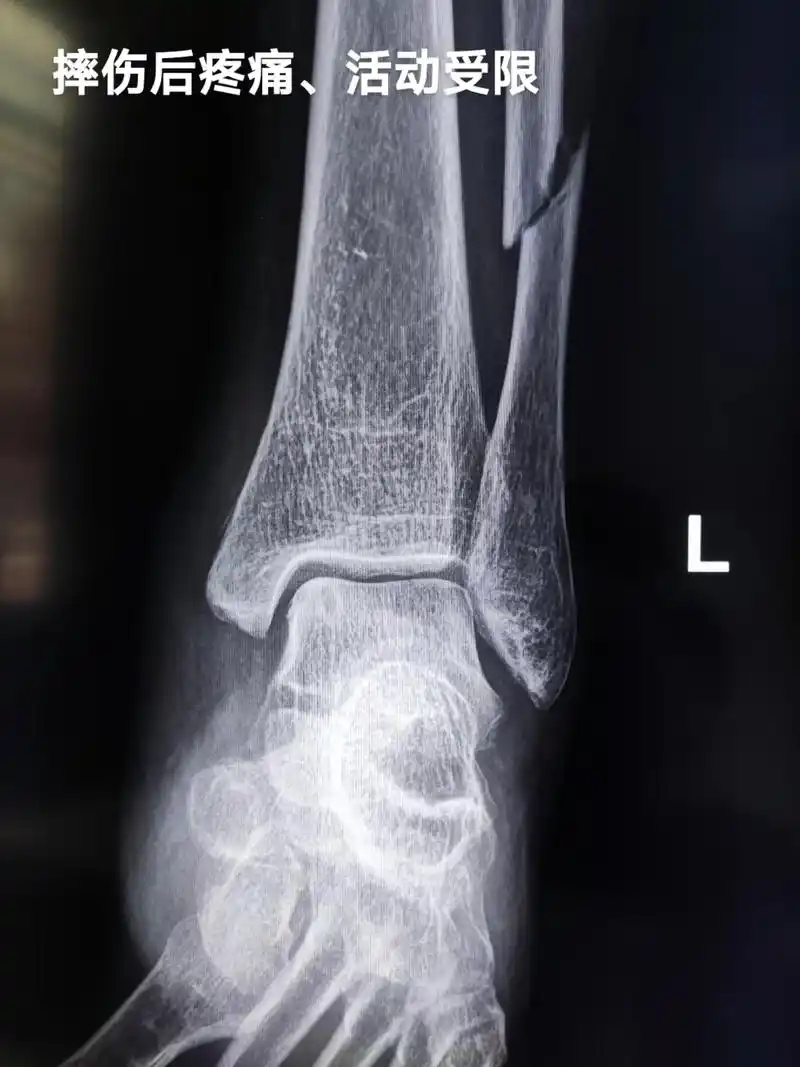

医学影像 摔伤致左小腿下段疼痛,活动受限,x线见腓骨骨折, - 抖音